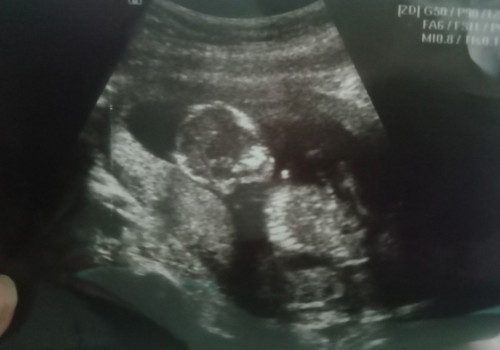

18Wน้องตัวเล็กไปมั้ยคะ

บ้านนี้ ซาวด์ 17w6d หมอบอก หนัก 227g หมอบอกน้ำหนักดีมาก คุณหมอที่แม่ไปซาวด์แจ้งน้ำหนักไหมค่ะ แต่ที่ดูในภาพลูกแม่ก็ไม่เล็กนะ

ไม่เล็กค่ะเท่ากับบ้านนี้เลยจ้า18+2สัปดาห์หมอบอกน้องจะโตขึ้นเรื่อยค่ะ

บ้านนี้19+4 เห็นเพศเเล้วค่ะ นน.290 กรัม หมอบอกนน.ดีมาก